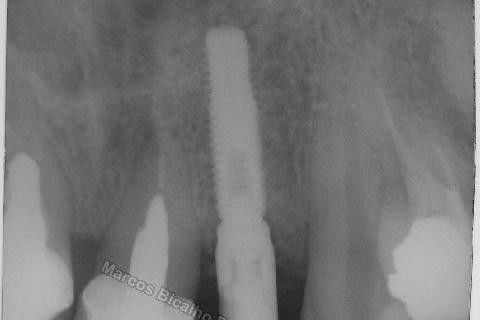

Este caso tem o objetivo de demonstração da técnica que normalmente sigo ; em casos onde ocorre fratura da raiz e consequentemente abscessos, com ou sem formação de fístula. Neste caso fiz a exodontia com preenchimento do alvéolo com biomaterial (osso bovino liofilizado + coágulo do paciente). Após 90 dias, mais ou menos, instalei o implante. Esperei mais 4 meses e realizei ontem (12/11/2010) a instalação do cicatrizador com o cuidado de preservar tecido mole, sem remoção de material, apenas afastando gengiva e "enrolando" a sobra de mucosa em direção a face vestibular, para promover conservação de papila futuramente. Se ocorrer excesso de papila, sem problema, remove-se um pouco, mas a intenção é não deixar faltar, o que resultaria em indicação para enxertos gengivais.

Fotos do caso